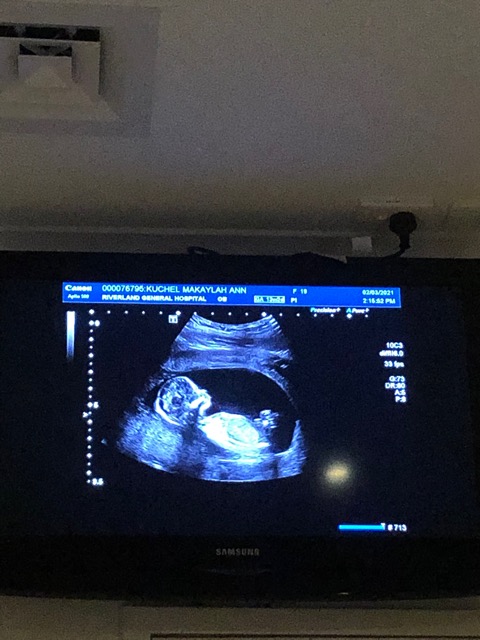

My 15 week alutrosund. I’m now 16 weeks today. We are hoping for a boy!